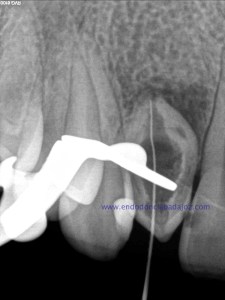

Se planteó el caso con una apertura del mismo y tratamiento de todo el conducto con puntas de ultrasonido desbridando las paredes e intentando no eliminar demasiado tejido dentinario. El primer paso sería conseguir una permeabilización del conducto: